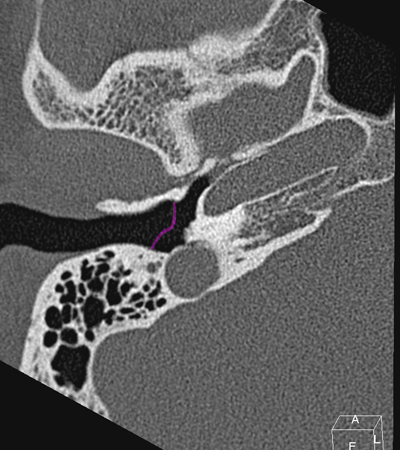

Horizontal petrous carotid Jugula bulb Sigmoid sinus Anterious wall of bony EAC (tympanic bone) Eustachian tube Tympanic membrane Facial nerve (f3), mastoid segment

Radioanatomy of Temporal bone